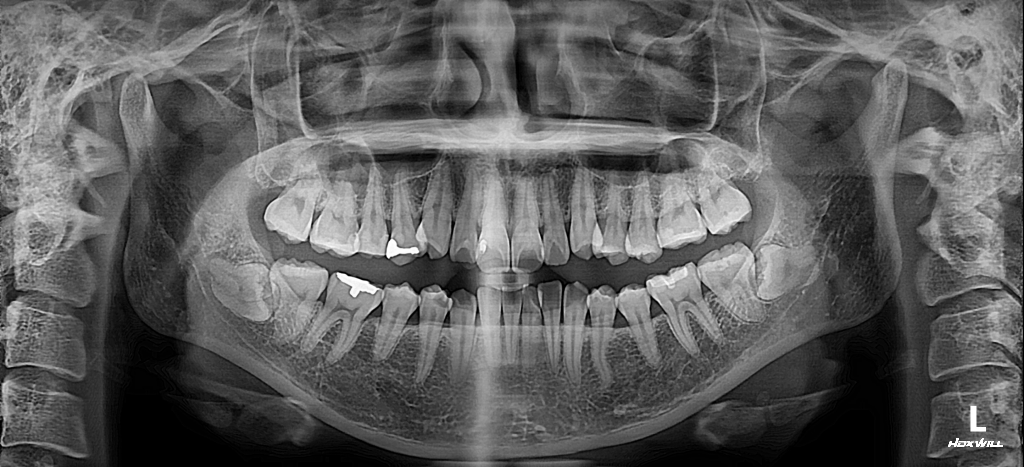

증상 없는 매복사랑니 뽑아야 할까요?

아래쪽에만 두 개 있는데 둘 다 누워있어요...

30대까지 아무 증상은 없는데 혹시 앞으로 신경을 건드린다거나, 어금니 뿌리 흡수할 위험성이 있는지 엑스레이상으로 확인가능할까요?

첨부해주신 사진으로 보아 양쪽 아래 사랑니는 수평매복 사랑니로 보여집니다.

사랑니를 뽑지 않을 경우 말씀해 주신 것처럼 두번째 큰어금니(7번) 뿌리에 영향을 줘서 치근흡수의 가능성이 있고요, 나중에 나이가 들었을 때 해당 부위에 증상이 생겨서 뽑고자 할 때 사랑니가 뼈에 착 달라붙어서(유착) 더 뽑기 힘들 수도 있고 그때 발치 후 회복이 더딜 수도 있습니다.

부분 맹출 되어 잇몸에 반쯤 파묻혀 있는 경우 그 부위가 관리가 쉽지 않고 음식물이 자주 낄 수 있습니다. 이럴 경우 잇몸에 염증이 생길 수 있고 통증이 동반될 수 있으며 심하면 악취가 날 수도 있습니다. 그렇기 때문에 부분 맹출된 사랑니는 여러모로 충치가 생기기 전이라도 예방적으로 발치를 권해드리나 완전히 뼈에 파묻힌 완전 매복 사랑니의 경우 예방적 발치가 반드시 이뤄져야 하는 것은 아닙니다.

현재 사랑니를 뽑고자 할 경우 아래턱을 지나는 신경과의 거리를 고려해봐야 하기 때문에 치과용 CT 촬영이 권장됩니다.